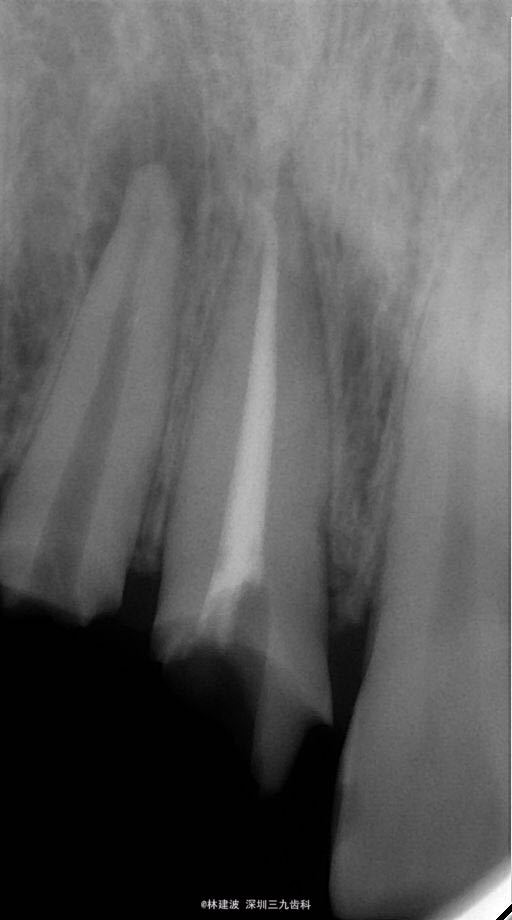

查体 辅查

12,11连冠,12继发龋。X片示:12根管内折断器械,根尖周阴影。